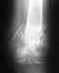

перелом внутренней лодыжки левой голени, левой м/берцовой кости с подвывихом стопы |

Уважаемые доктора!Мне срочно нужна Ваша консультация!Перелом оказался очень сложным,и, кажется упущено время.Всё ещё надеюсь на возможность консервативного лечения. 1 января подскользнулась и, упав, сломала ногу.В неотложке мне был наложен лангет.Живу в деревне, и в больницу добралась лишь25.01. Нога не беспокоила совсем.Но Р-грамма показала перелом внутренней лодыжки,м/берцовой кости с подвывихом стопы.Хирург выписал направление в вашу клинику на консультацию.Не представляю, как я смогу на костылях добраться к вам.Помогите пожалуйста хотя бы виртуальной консультацией!Снимки перешлю.Я в панике!

Действительно, взаимоотношения в суставе требуют восстановления. Добраться к нам проблем не составляет, привозят не то что ходящих на костылях, а и лежачих. Бывает, за тысячи км.